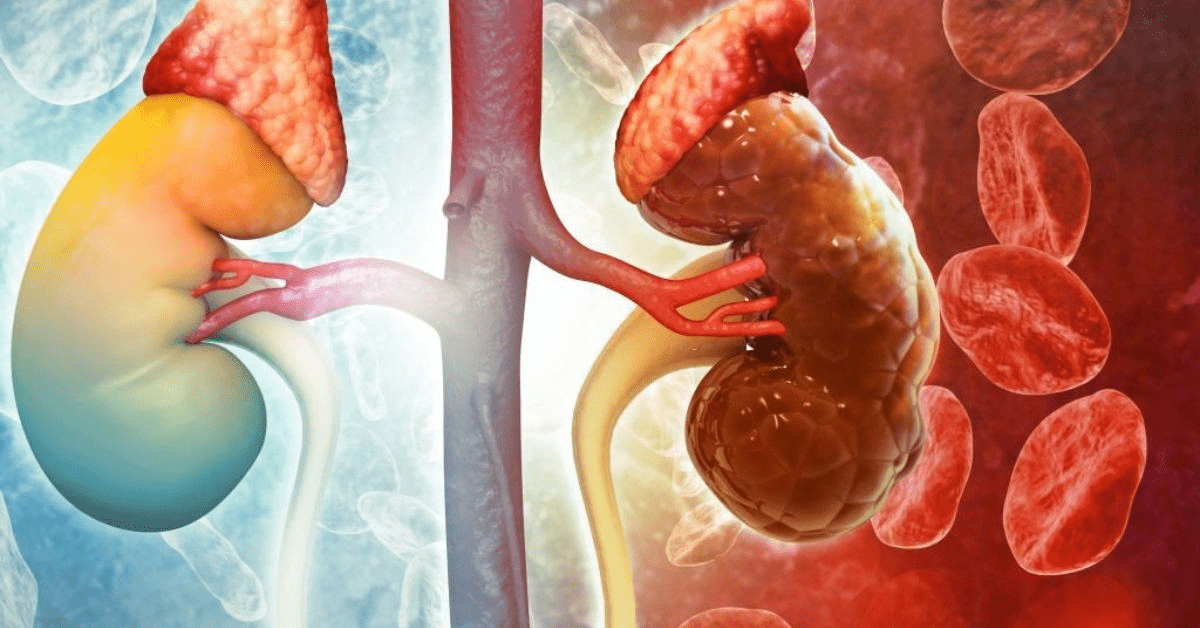

Your kidneys filter waste, balance fluids, and regulate blood pressure every minute of every day. When they get damaged—from diabetes, high blood pressure, infections, or long-term strain—tissues can scar, function declines, and in advanced stages, chronic kidney disease (CKD) sets in. “Dead” kidneys refer to severely scarred or non-functioning tissue that doesn’t regenerate like skin or liver might. Once significant scarring occurs, the kidneys can’t fully repair themselves naturally. Medical management focuses on slowing progression, managing symptoms, and in severe cases, dialysis or transplant. No single food regenerates lost nephrons (the kidney’s filtering units) or reverses end-stage damage permanently on its own.

The viral posts often show pitted, damaged kidneys transforming into healthy ones after “spinach treatment.” These images are typically illustrative or edited for shock value, not real patient scans tied to spinach consumption. Research does not support claims that spinach—or any plant—can regenerate dead kidney tissue forever.